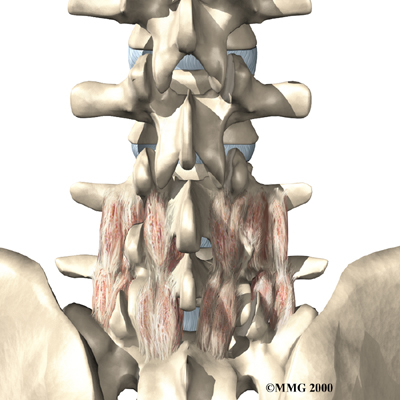

The human spine is formed by 24 spinal bones, called . Vertebrae are stacked on top of one another to form the spinal column. The spinal column gives the body its form. It is the body's main upright support. The section of the spine in the lower back is known as the .

The lumbar spine is made up of the lower five vertebrae. Doctors often refer to these vertebrae as L1 to L5. These five vertebrae line up to give the low back a slight inward curve. The lowest vertebra of the lumbar spine, L5, connects to the top of the sacrum, a triangular bone at the base of the spine that fits between the two pelvic bones. Some people have an extra, or sixth, lumbar vertebra. This condition doesn't usually cause any particular problems.